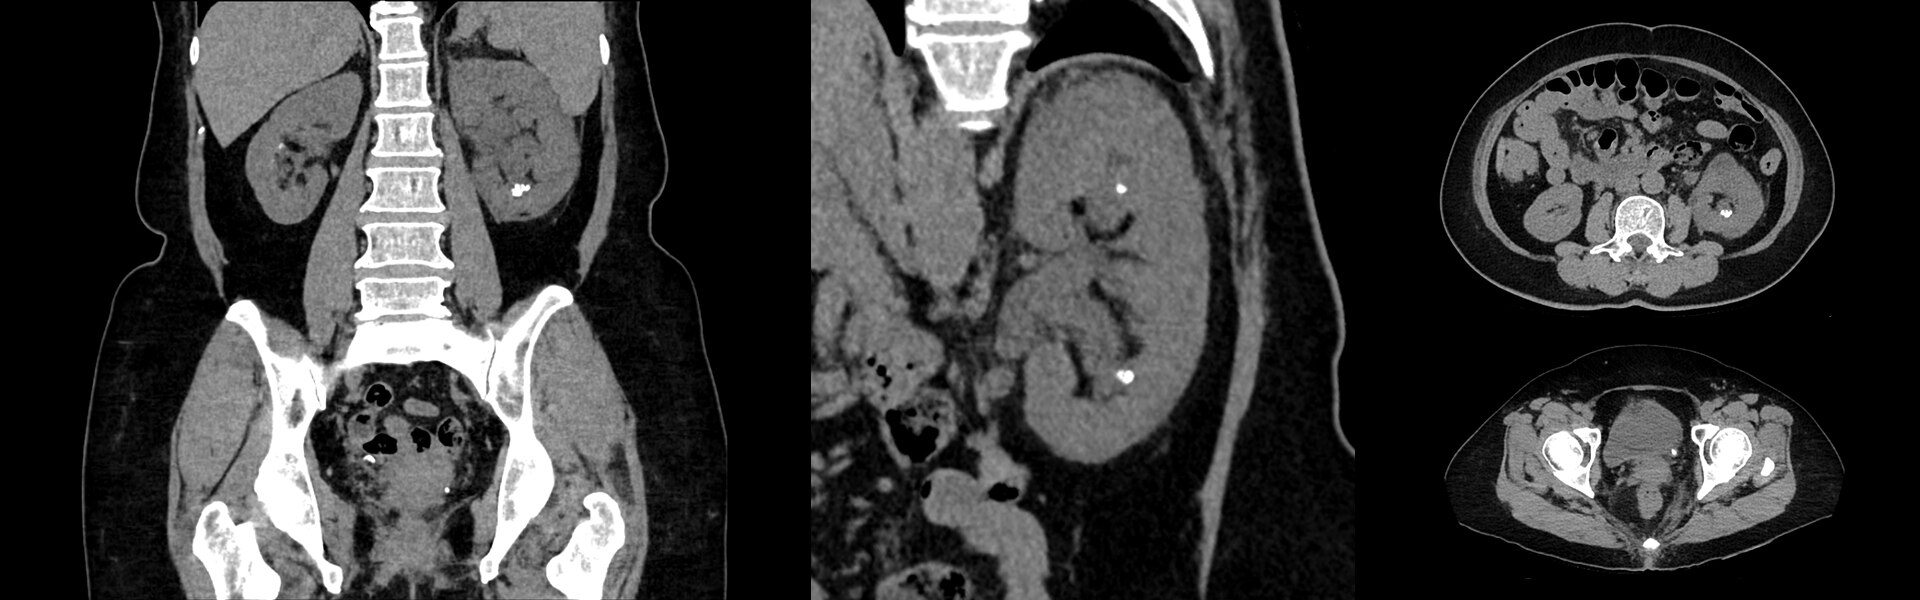

Imagens Clínicas

Várias lesões pequenas nas pernas e ao longo do pescoço.

A lesão da orelha direita mede na TC 3,5 mm. Tumor no quadril comendo o osso.

Cervical direito medindo 6 mm.

Acne visto nas costas.

Pulmão direito, virilha direita e tumor atrás do joelho direito.

Câncer na cabeça e pescoço.

Pós-radioterapia, progresso do câncer. Pequeno câncer de mama.

Linfonodos ávidos por FDG na axila esquerda (vacinação contra COVID-19).